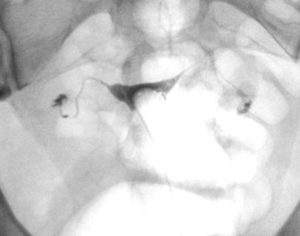

However, I did have an HSG test done afterwards and both tubes are open!